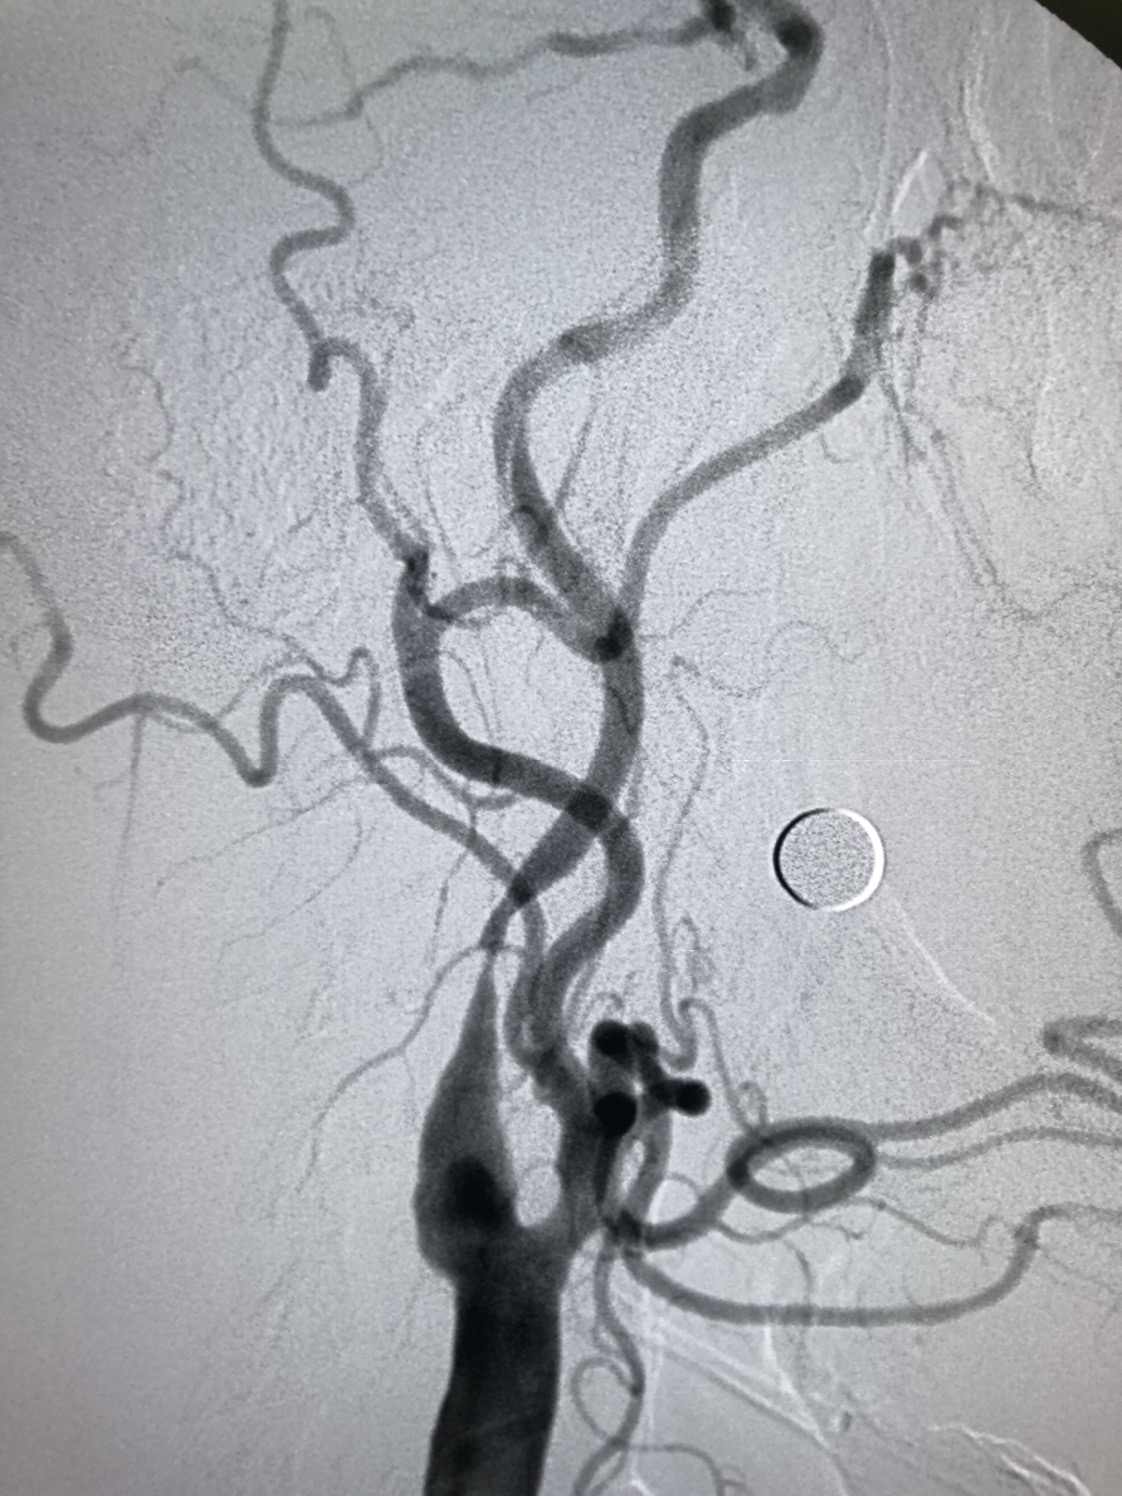

DSA:右侧颈内动脉窦部以远线性狭窄,窦部可见粥样硬化斑块,局部溃疡斑形成,动态可见造影剂滞留,颅内血管显影差。

DSA:颅内血管显影差。